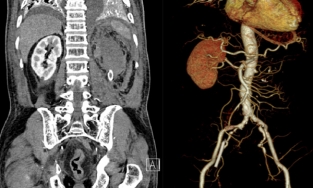

Người đàn ông mắc căn bệnh phình động mạch hiếm gặp